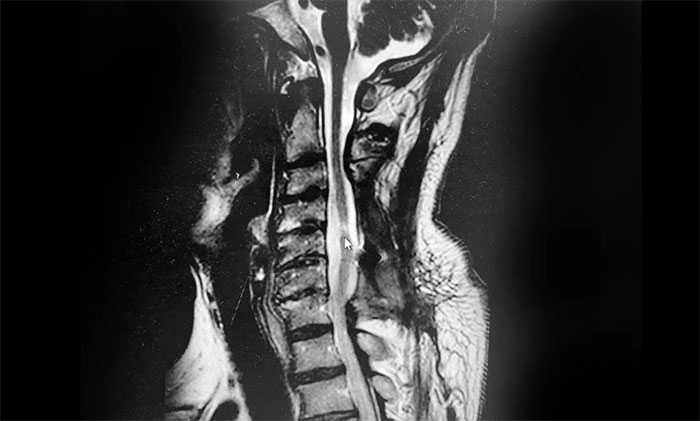

到就近医院救治,急诊查颈椎CT示:患者颈3-7椎体略变扁、颈椎反弓、项韧带钙化。颈椎脊髓损伤发生四肢瘫痪者,往往病情严重,常发生呼吸系统并发症,病死率高,对其治疗刻不容缓。其后,老刘转外院立即接受了颈椎后路减压融合内固定手术。

▲患者颈髓损伤、颈椎反弓

在外院经抗感染、营养神经等治疗后,老刘病情趋于稳定,但仍然遗留下高位截瘫,四肢几乎无法活动,只能长期卧床,留置导尿管排尿。